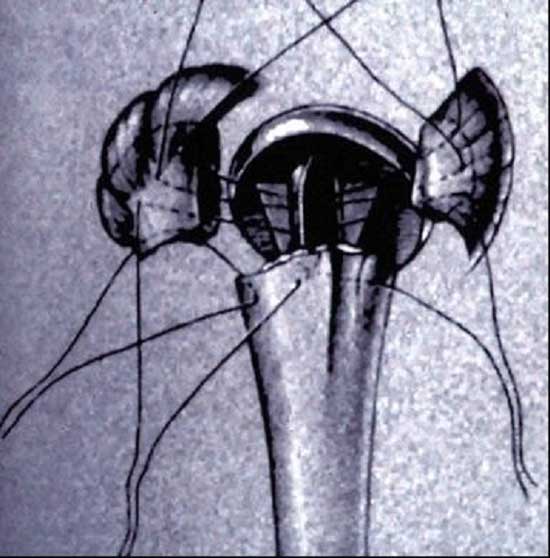

在肱骨近段有骨缺损、解剖标志失去时,首先保证假体的

正确旋后和插入的深度,在肱骨近端钻孔穿粗的不吸收缝线

• 大结节用粗的不吸收缝线,固定到假体的颈部

• 骨块位于假体领的下方且无很大张力

修复关节囊、肩胛下肌、三角肌、胸大肌、联合腱